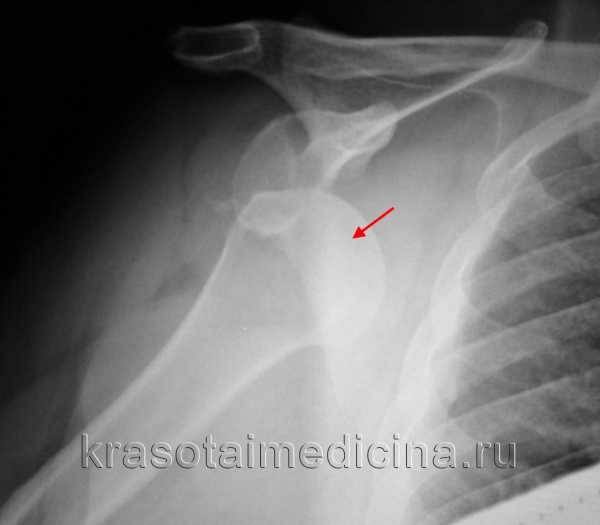

(Слева) На рентгенограмме в передне-задней проекции Ниера визуализируется неконгруэнтный плечевой сустав с патологическим перекрытием плечевой кости и суставной впадины. Кроме того, определяется симптом борозды, указывающий на обратный вдавленный перелом Хилла-Сакса переднемедиальной области головки плечевой кости.

(Справа) На аксиллярной рентгенограмме у этого же пациента подтверждается заблокированный или хронический задний вывих. Симптом бороздки на передне-задней рентгенограмме складывается за счет сагиттально ориентированной вдавленной костив, которая образует латеральный край обратного перелома Хилла-Сакса.

2. Рентгенография при заднем вывихе плеча:

• Передне-задняя проекция:

о Симптом бороздки:

- Вертикальный линейный склероз медиальной области головки плечевой кости

- Встречается при 75% задних вывихов

- Возникает вследствие обратного вдавленного перелома Хилла-Сакса:

Вдавление кости вдоль края перелома параллельно рентгеновскому лучу

о Симптом маленькой луковицы:

- Малый бугорок с медиальной стороны, а большой бугорок с латеральной стороны: проксимальный конец плечевой кости напоминает форму маленькой луковицы

- Вследствие значительной внутренней ротации

о Симптом ободка:

- Расширенный плечевой сустав

- 6 мм, наблюдается при 2/3 задних вывихов

о Потеря нормального полулунного перекрытия головки плечевой кости и суставной впадины:

- Вследствие латерального смещения вывихнутой головки плечевой кости